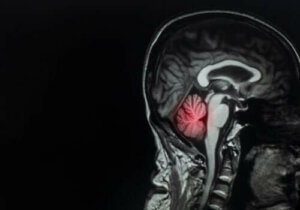

I den forstand, er det spændende at bemærke, at spredningen af hjernemetastaser er proportional med blodgennemstrømningen i det påvirkede område. Det er placeret i forhold til de følgende procentdele:

- 80% af læsioner i hjernen

- 15% i lillehjernen

- 5% i hjernestammen